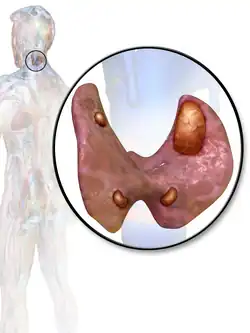

A human being usually has four parathyroid glands located on the posterior surface of the thyroid in the neck. In order to maintain calcium metabolism, the parathyroid glands secrete parathyroid hormone (PTH) which stimulates the bones to release calcium and the kidneys to reabsorb it from the urine into the blood, thereby increasing its serum level. The action of calcitonin opposes PTH. When a parathyroid adenoma causes hyperparathyroidism, more parathyroid hormone is secreted, causing the calcium concentration of the blood to rise, resulting in hypercalcemia.[2]

Before surgery is attempted, the affected glandular tissue must be located. Though the parathyroid glands are usually located on the back of the thyroid, their position is variable. Some people have one or more parathyroid glands elsewhere in the neck anatomy or in the chest. About 10% of parathyroid adenomas are ectopic, located not along the back of the thyroid but elsewhere in the body, sometimes in the mediastinum of the chest.[11] This can make them difficult to locate, so various imaging techniques are used, such as the sestamibi scan, single-photon emission computed tomography (SPECT), ultrasound, MRI,[11] and CT scans.[11][13] sometimes parathyroid adenomas can be ablated by ethanol injection, laser or radiofrequency guided by ultrasound.